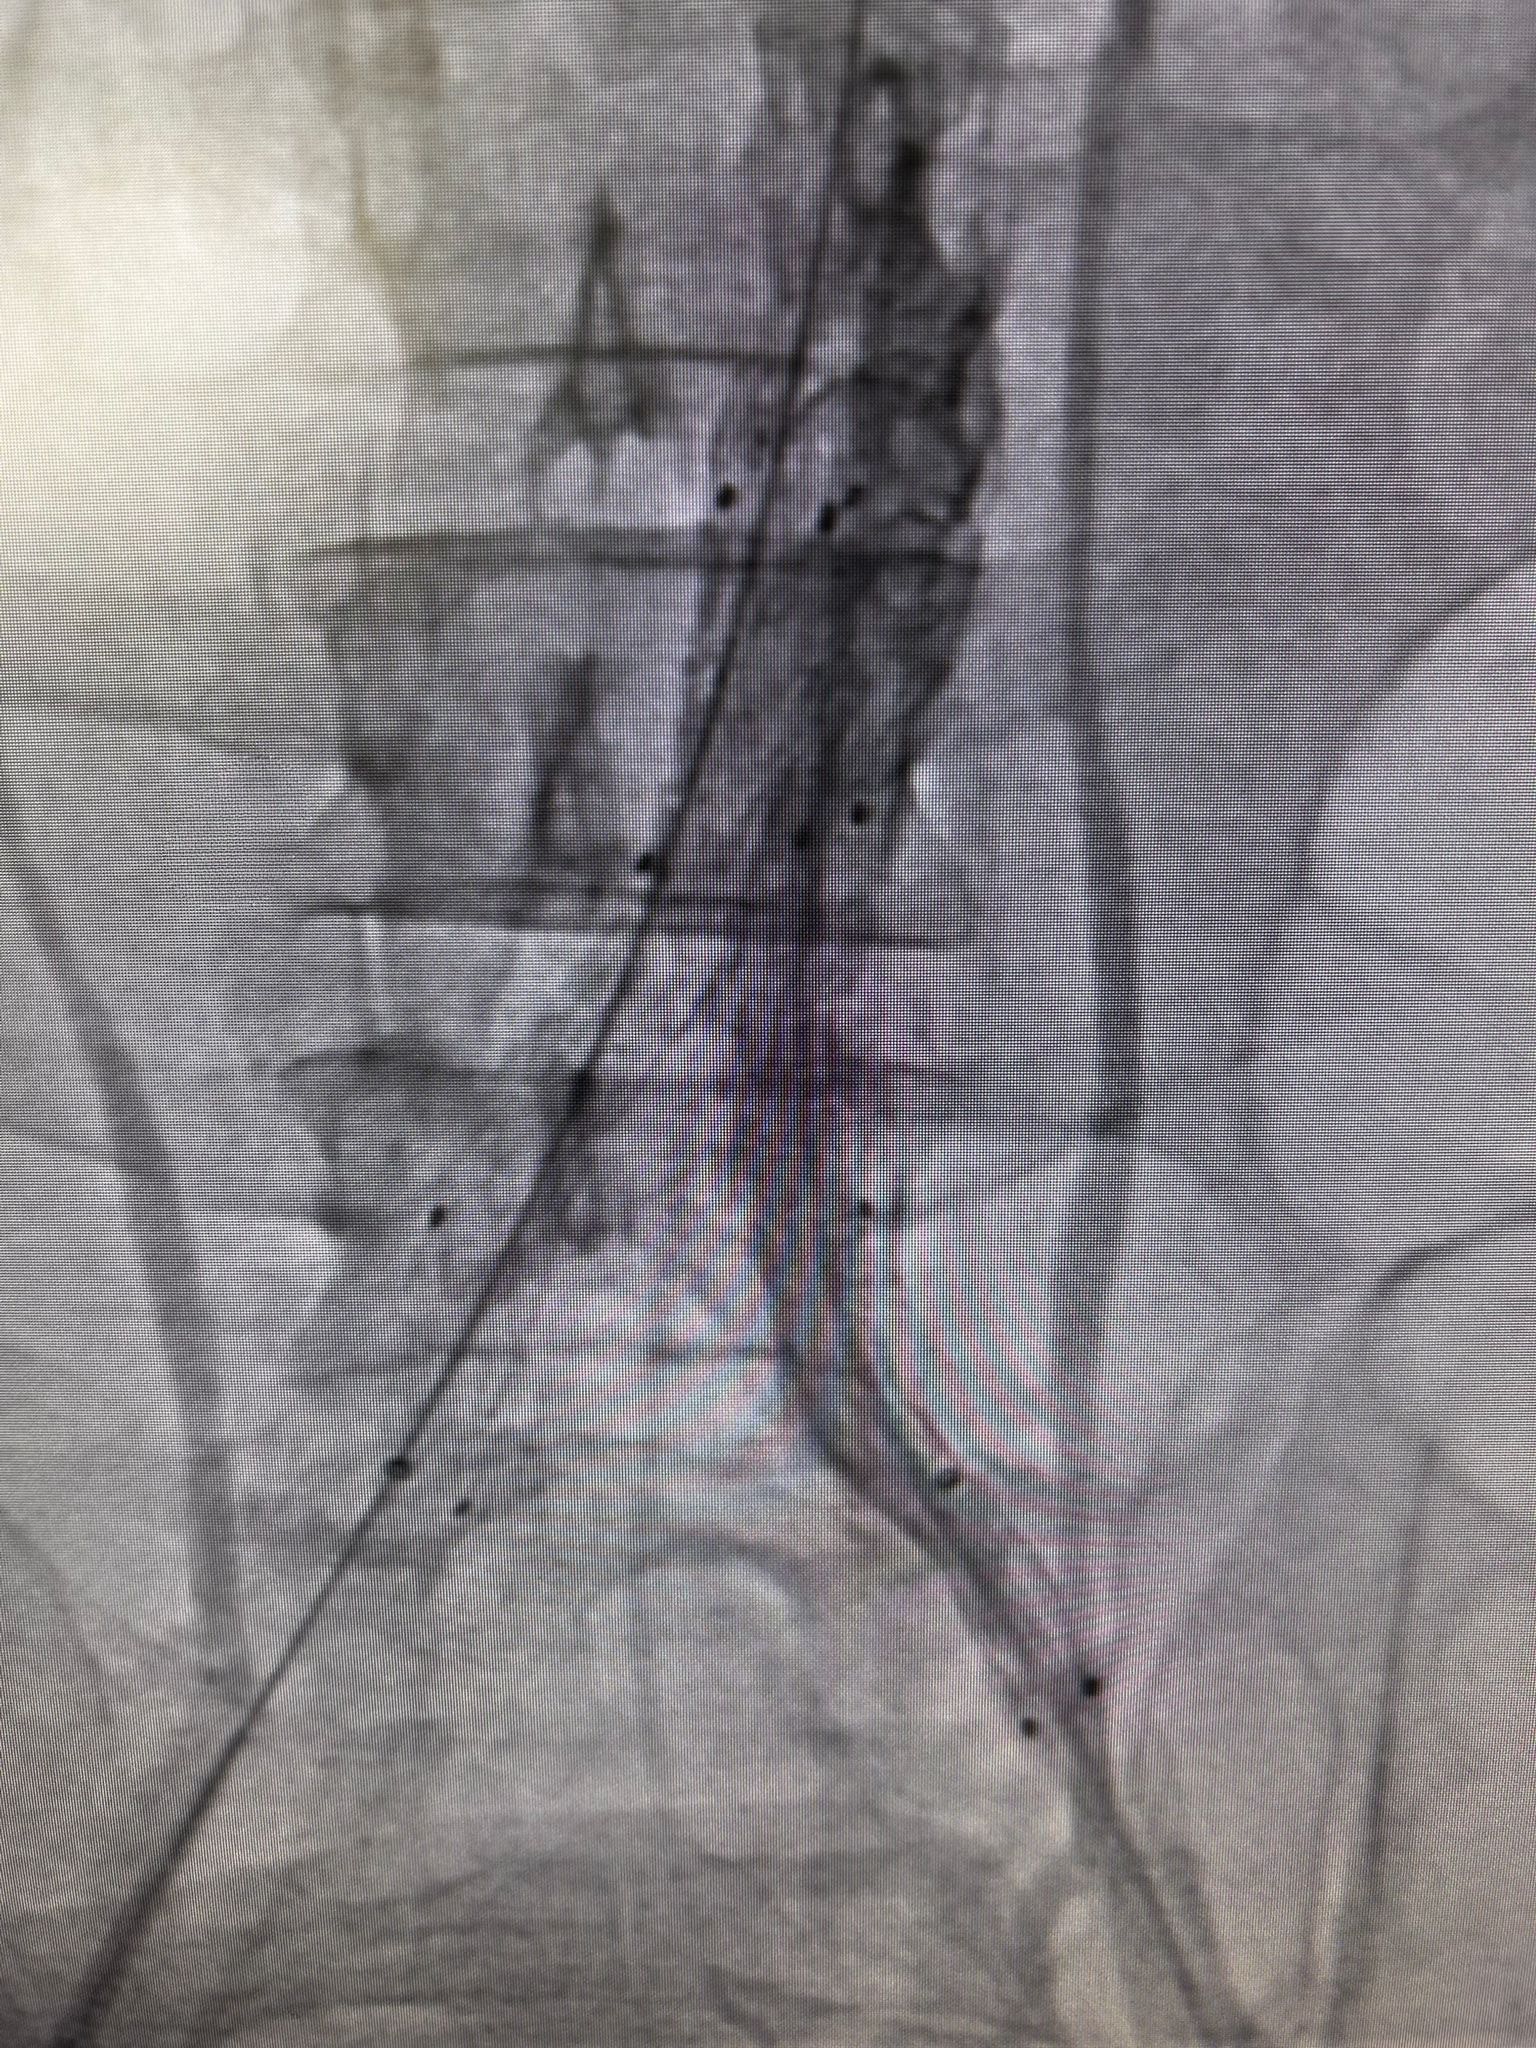

Hasta, Kalp ve Damar Cerrahisi Uzmanı Op. Dr. Elmas Üreyen tarafından kapalı yöntemle tedavi edildi. Damar içinden girilerek yapılan işlem sırasında, yırtılan ana damarın içine özel bir stent yerleştirildi ve damar içten onarıldı. Açık ameliyata gerek kalmadan gerçekleştirilen bu yöntem sayesinde hasta kısa sürede rahatladı.